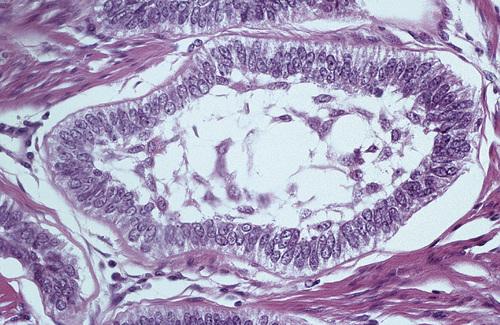

Histopathologic Features

- loosely arranged fibrous connective tissue wall

- islands or cords of odontogenic epithelial rests

- two to four layers of flattened nonkeratinizing cells

- focal areas of mucous cells in epithelial lining

This noninflamed cyst shows a thin, nonkeratinized epithelial lining and a loosely arranged fibrous connective tissue wall.

dentigerous cyst, noninflamed

This inflamed cyst shows a thick epithelial lining with hyperplastic rete ridges and diffuse chronic inflammatory infiltrate.

dentigerous cyst, inflammed

This cyst shows scattered mucous cells within the thin epithelial nonkeratinized epithelial lining.

dentigerous cyst